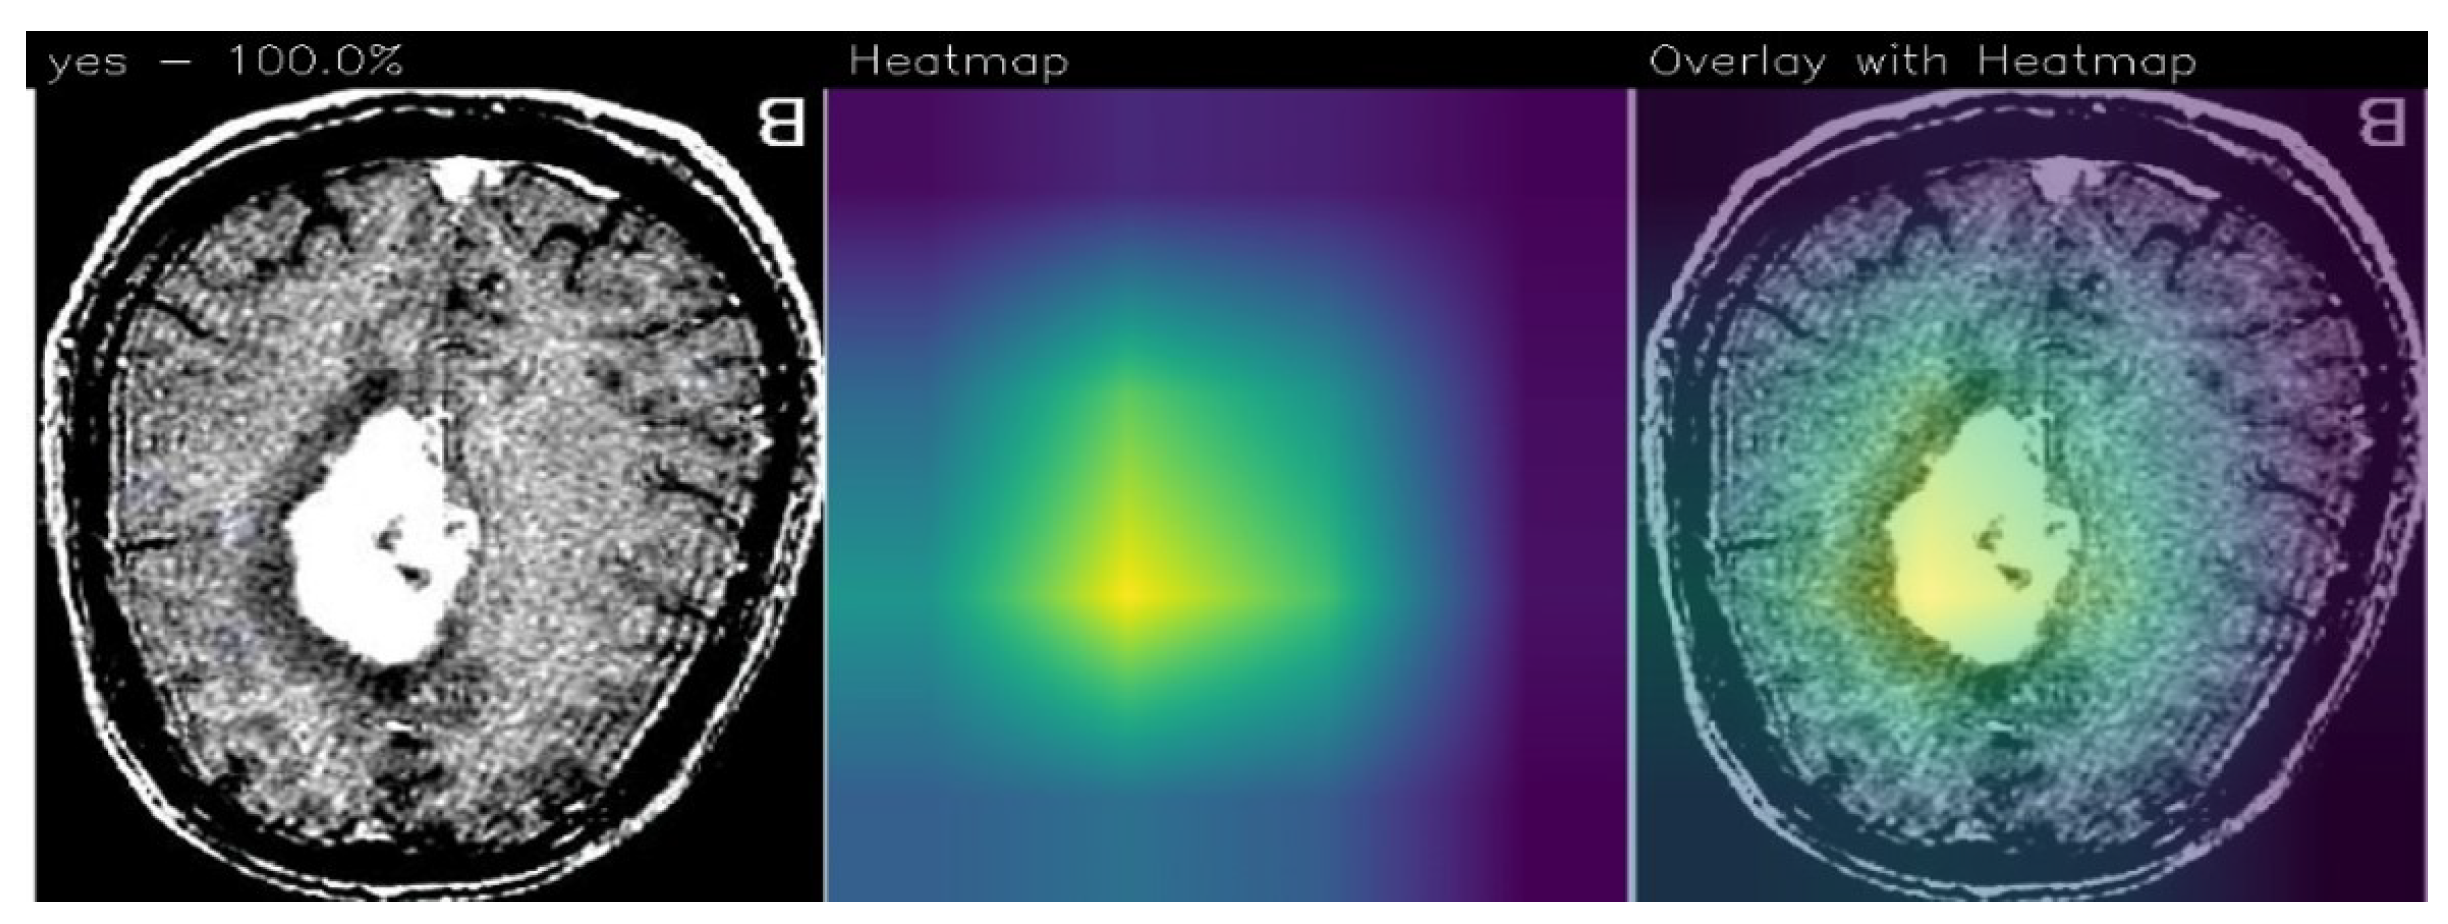

In relation to explainability, in Figure 4 we show an example of localisation performed by the proposed method, in particular, there are areas (in yellow) where, from the proposed ResNet50 model’s point of view, there is disease localisation.

Figure 4.

An example of prediction performed using the proposed method with the detail of tumor localisation from the ResNet50 model’s point of view.

The GradCAM is an interpretability technique used to highlight areas in an image that contribute the most to a model’s prediction. It assigns different color intensities to these areas based on their importance from the model’s perspective.

In the context of brain tumor detection, GradCAM can help identify regions in the image that are particularly symptomatic of a brain tumor or are indicative of pathology. The technique assigns a yellow color to areas of extreme importance, which are highly influential in the model’s prediction and strongly associated with the presence of a brain tumor. These areas are considered particularly symptomatic.

Areas of minor importance, but still relevant to the pathology, are assigned a green color by GradCAM. These regions may contribute to the overall prediction but to a lesser degree compared to the yellow areas. They still provide valuable information related to the presence or characteristics of the pathology.

On the other hand, GradCAM uses a purple color to indicate areas that are not of interest for the detection of pathology. These regions are considered less important and do not significantly influence the model’s prediction.

By applying GradCAM, researchers and medical professionals can visualise and understand which areas of an image are driving the model’s decision-making process. This can provide insights into the features or patterns that the model considers indicative of a brain tumor or pathology, enhancing the interpretability and trustworthiness of the model’s predictions.

As we note, the Grad-CAM highlighted the areas related to brain cancer (i.e., the white ones), by showing the effectiveness of the proposed method in brain cancer detection and localisation. For this reason, we think that Grad-CAM may provide explainability behind the model’s prediction, as it highlights the area that the model judged to be symptomatic of the brain tumor.

One of the most interesting advantages deriving from the adoption of Grad-CAMs is the possibility of having the areas of the image responsible for a determined prediction (in this case, of brain cancer) starting from a model built for the classification task of images. The results relating to localisation do not appear in the paper, as the dataset provided contained only the image label and no localisation details. In any case, we submitted the images with the areas highlighted by the Grad-CAM to three expert radiologists belonging to different hospitals, and they confirmed that the Grad-CAM highlights the correct area of the pathology.